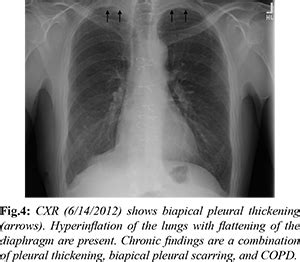

Pleuroparenchymal Fibroelastosis following Asbestos Exposure